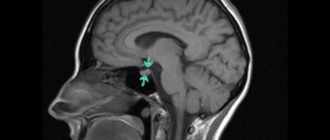

Мрт гипофиза: что показывает, зачем и как проводят, показания и противопоказания, расшифровка результатов Магнитно-резонансная

Мрт гипофиза и мозга что показывает, заключение, пролактин Здоровье стало подводить: частые головные боли,